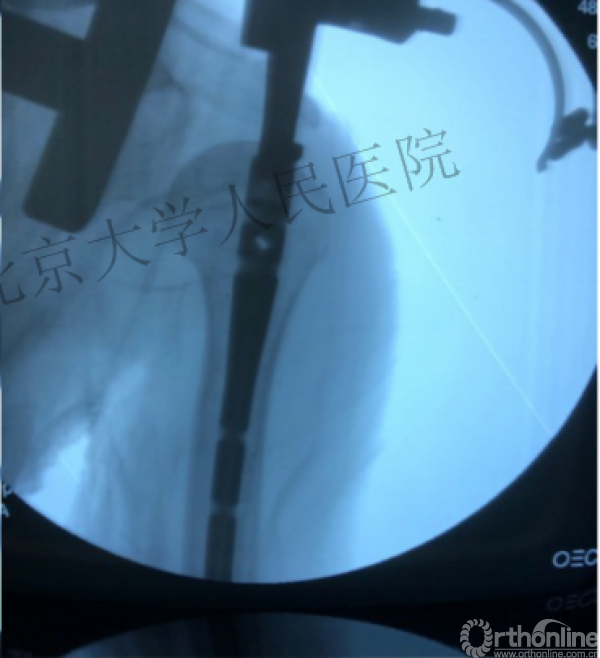

透视肱骨头正位、侧位确定进针点

术中片